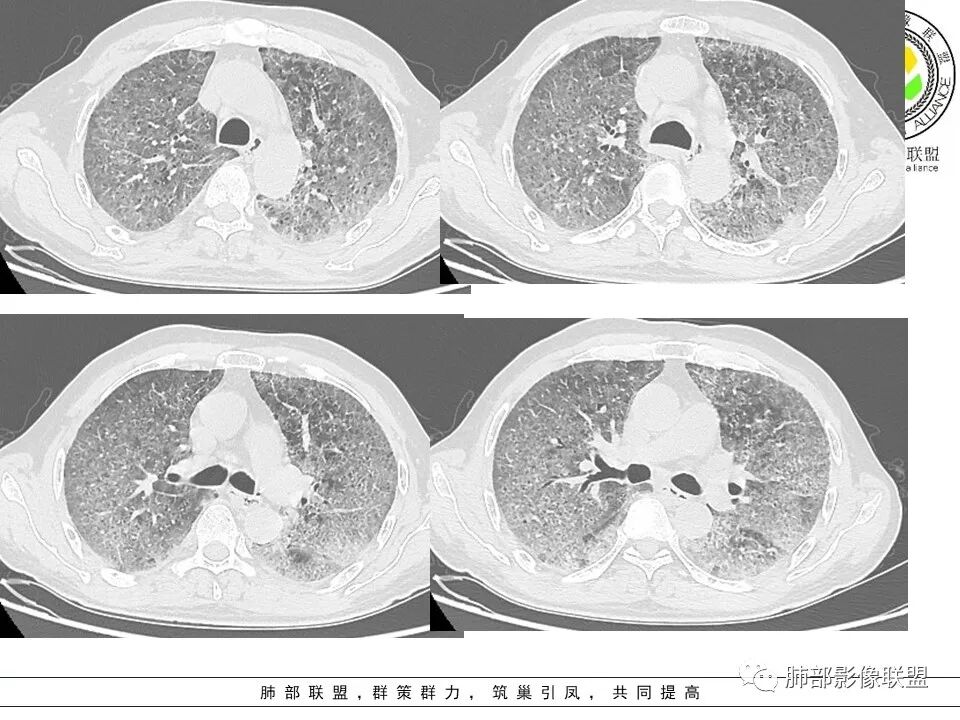

徐婕:双肺弥漫磨玻璃,铺路石,部分斑片实变。病程一年,血白细胞增高,考虑肺泡蛋白,合并双肺感染?鉴别腺癌

八爪:弥漫分布磨玻璃密度影,小叶间隔增厚,典型铺路石征,考虑PAP伴发感染性病变,鉴别特发性间质性肺炎,弥漫性腺癌,建议支气管灌洗;左肺上叶舌段不规则团片状阴影,显示不清,密切随访

笨丫头:双肺弥漫磨玻璃影,间质性改变,既往有煤炭工作史,考虑尘肺,左肺占位,边界不清,不除外合并肿瘤,腺癌?

小谢:慢性病程,无发热,双肺弥漫性病变,GGO,铺路石征,首先考虑PAP,鉴别肺腺癌

一米阳光:中老年男性,病程长。双肺弥漫性ggo,小叶间隔明显增厚,铺路石样改变,考虑PAP,鉴别pcp。建议支气管镜检查并灌洗。病史有尘肺接触史,排除尘肺合并结核

郑氏刀刀:双肺弥漫性磨玻璃影,伴铺路石征,下叶为主,且见斑片实变影,白细胞高,结合执业史,尘肺,PAP伴感染,腺癌待排。

小景:双肺弥漫磨玻璃影,小叶间隔增厚,呈碎石路征。患者粉尘接触史,考虑PAP。左肺舌段病灶,抗感染无吸收,腺癌待排。

小赵:中老年男性患者。慢性病程,多次咳黄痰,治疗效果一般,反复发生。CT表现为双肺弥漫磨玻璃样改变,并呈细网格样铺路石状改变,上下肺无明显差异。双下肺为主多发渗出实变,边界不清,抗炎治疗后病变吸收不明显,局部似有进展。考虑肺泡蛋白沉积症基础上合并感染。肿瘤标志物高,中老年患者,肺炎型肺癌不除外。

上肺为主小叶中心型肺气肿——吸烟

碎石路征,下肺为主

肺部结节

左上叶斑片状高密度影

南边:只有GGO+网格(小叶间隔增厚),然后就是分布的问题

1、GGO+网格——碎石路征

2、分布无特定位置,较随机

3、可有少许实变——部分与层厚有关

4、小叶间隔内静脉增粗

5、病灶较多时部分可见重力趋势